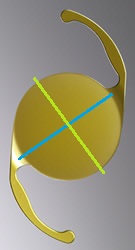

先日ハードレンズを処方した方の写真です。

先日ハードレンズを処方した方の写真です。